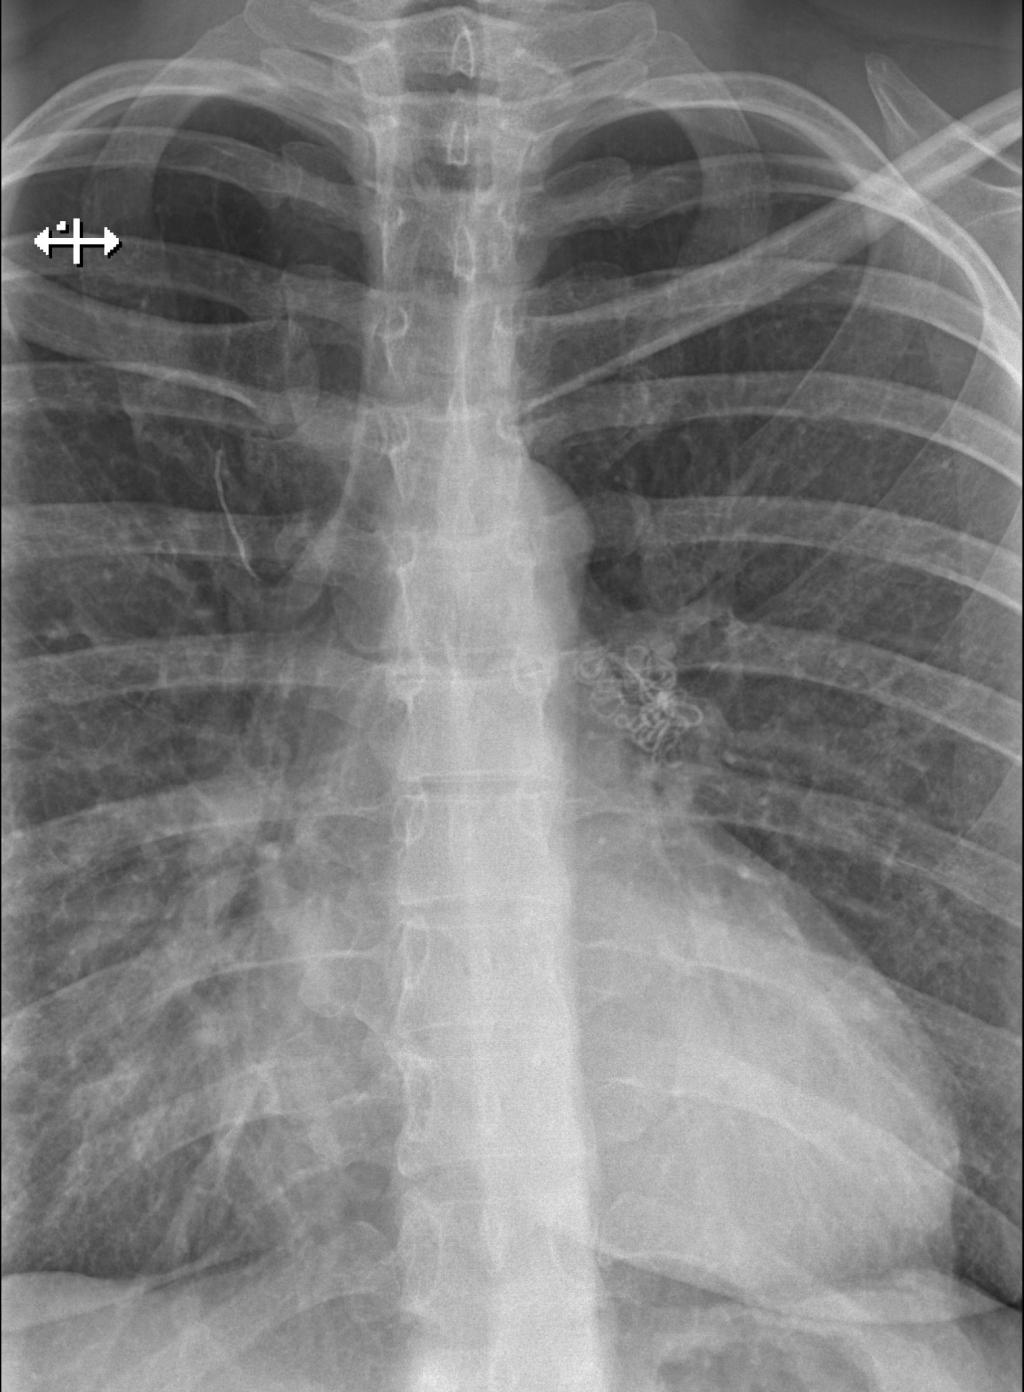

Een 36-jarige vrouw komt bij de huisarts met langdurige hoestklachten en dyspneu. Tien jaar geleden heeft zij een spondylodese ondergaan; een jaar geleden is een losse schroef gefixeerd met cement. Na een kuur amoxicilline houden de luchtwegklachten aan. Er volgt een thoraxfoto.

Wat is de diagnose?